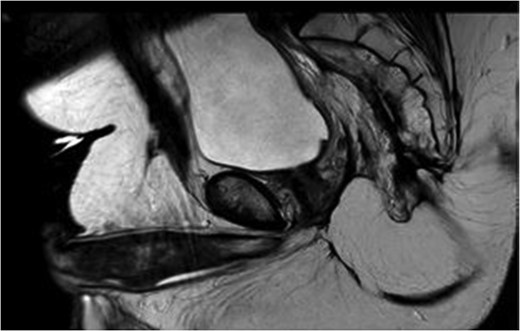

MRI pelvis large field T2 sagittal image through penile shaft showing the lesion involving the corpora cavernosum with extension in the spongiosum.

It is still a controversial subject the reason why the penis, despite its vascularization is a rare site for metastasis. It has been postulated that the route of metastasis include retrograde venous or lymphatic spread, local direct extension, arterial embolism or instrumental spread [1, 2, 4]. Currently the most accepted theory is the mechanism that involves retrograde venous spread from pudendal to the dorsal venous system of the penis [2, 4]. The most common type of presentation is malignant priapism followed by urinary retention, penile nodules, ulceration, perineal pain, oedema, infiltrative enlargement, dysuria and haematuria, with the corpora cavernosa being the most common site of metastasis and the glans and corpus spongiosum infrequently involved [1]. Our case respected the above mentioned cavernosal involvement but also had mild extension into the corpus spongiosum, more to the fact that this isolated metastatic penile neoplasm is extremely rare.